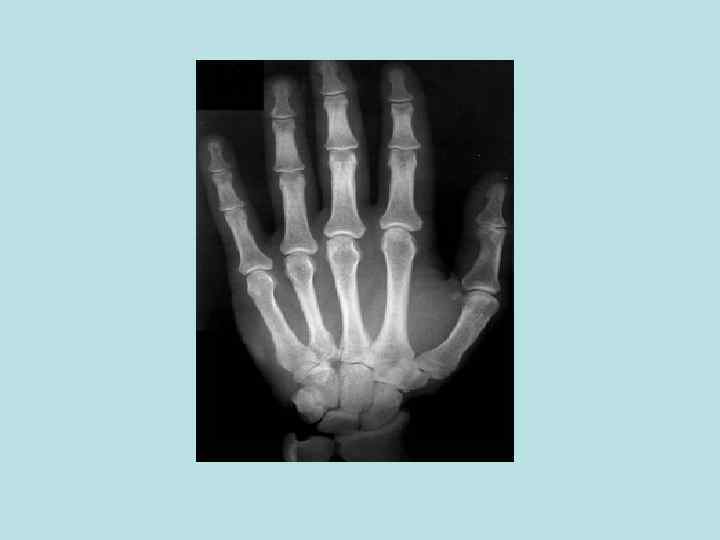

Объект и методы исследования в анатомии • Неживые объекты • Живые объекты - - - Вскрытие трупов и препарирование Бальзамирование Распилы частей тела и органов Метод инъекции и коррозии Изготовление сухих препаратов по В. Л. Груберу и Б. А. Шору и др. Просветление тканей органов Метод бьющей капли Макро - микроскопия Пластинация органов и трупов Гистотопография Световая и электронная микроскопия Соматоскопия Антропометрия Рентгеноанатомия (рентгенография, томография, электрорентгенография) - Эхолокация Компьютерная томография Магнитно-резонансная томография Эндоскопия Эксперименты на животных Математические и статистические методы